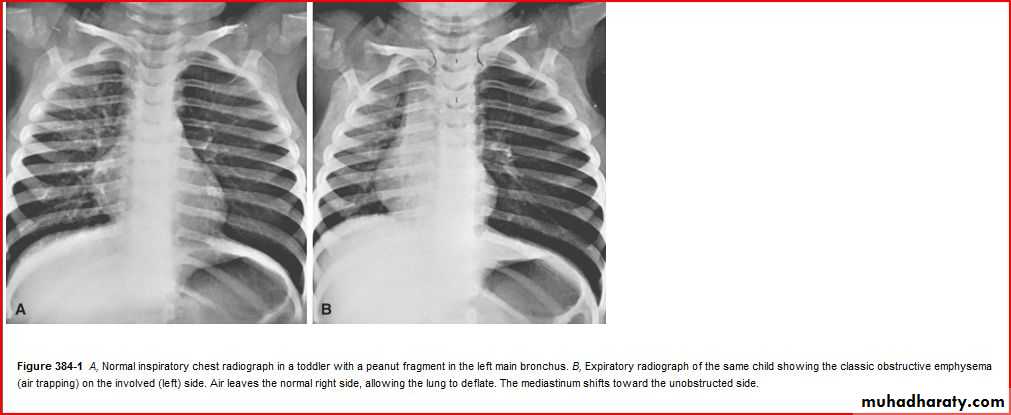

Hx of FB

A showing normal x rayB xray during expiration showing lt. lung emphysema make shifting of mediastinum